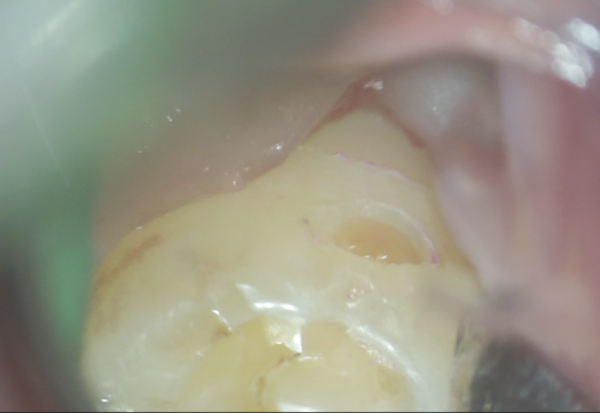

ピッタリ当たっているのがわかります。

ピッタリ当たっているのがわかります。

この道具がそもそも所持している先生がいないのと、使用も難しいです。

健康な部分を削らずに虫歯だけ削るのがとても難しいです。

一般の治療だと健康な部分も大きく削って見やすくしたり、金属を詰めるために表面積を大きくするために大きく削って詰めることになります。